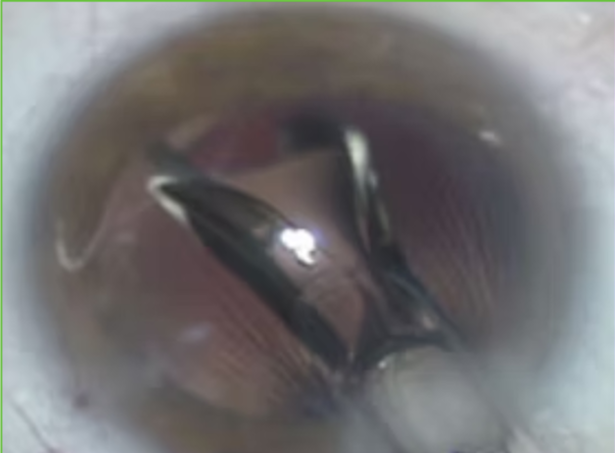

Facoemulsificação Aspirando

Implante da Lente Injetável